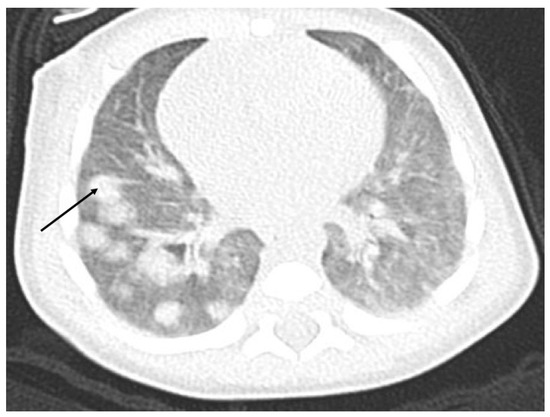

The ultrasound examination performed on admission in the oncological ward showed a massive hypodensive lesion in the right lobe of the liver, which was 5 cm in diameter. The lung X-ray indicated three circular metastatic lesions. Chest and abdominal computed tomography (CT) showed numerous (about 50) metastatic lesions in both lungs, and a liver tumor 5.2 cm × 3.7 cm × 4.8 cm in the right lobe. Lung window axial CT image shows multiple pulmonary rounded nodules of variable size, scattered throughout both lungs (Figure 1).

Figure 1. Chest CT with numerous metastatic lesions in both lungs.